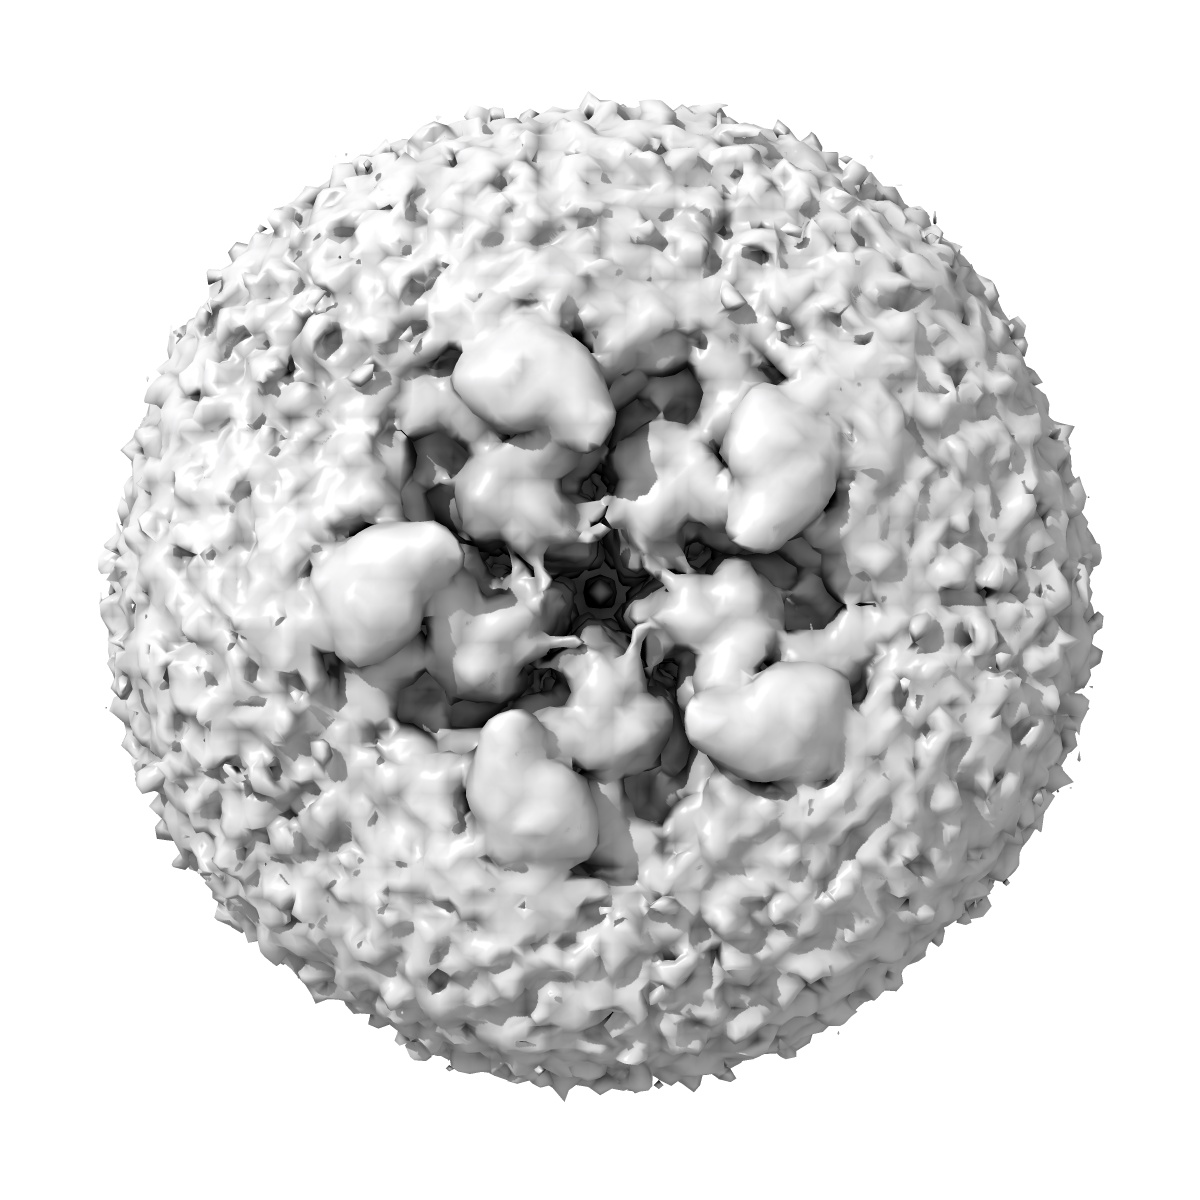

Cryo-EM structure of the beta3 homomeric GABA(A) receptor in complex with HSM in the short-lived symmetric bound-closed state (C5)

Sample: Cryo-EM structure of the beta3 homomeric GABA(A) receptor in complex with HSM in the short-lived symmetric pre-active state (C5)

Cryo-EM structure of the beta3 homomeric GABA(A) receptor in complex with HSM in the short-lived symmetric pre-active state (C5)

Deposition Authors: Mihaylov DB , Malinauskas T , Aricescu AR